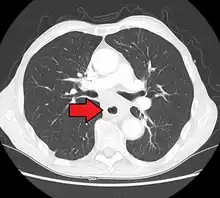

Additional testing is needed to assess how much the cancer has spread (see § Staging, below). Computed tomography (CT) of the chest, abdomen and pelvis can evaluate whether the cancer has spread to adjacent tissues or distant organs (especially liver and lymph nodes). The sensitivity of a CT scan is limited by its ability to detect masses (e.g. enlarged lymph nodes or involved organs) generally larger than 1 cm.[43][44] Positron emission tomography is also used to estimate the extent of the disease and is regarded as more precise than CT alone.[45] PET/MR as a novel modality has shown promising results in preoperative staging with fair feasibility and good correlation in comparison to PET/CT. It can enhance tissue differentiation with lowering the radiation dose to the patient.[46] Esophageal endoscopic ultrasound can provide staging information regarding the level of tumor invasion, and possible spread to regional lymph nodes.

Contrast CT scan showing an esophageal tumor (axial view)

Contrast CT scan showing an esophageal tumor (coronal view)